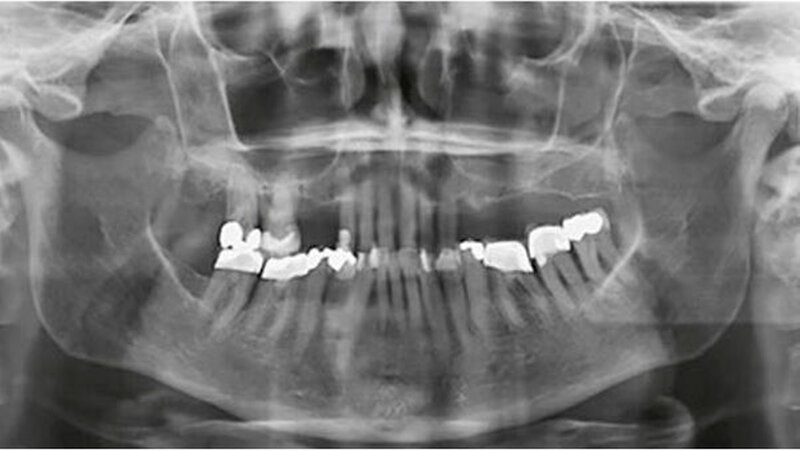

Als sich die Patientin in einer allgemeinmedizinisch stabilen Situation befand, erfolgte eine Vorstellung mit Verdacht auf einen oralen Fokus in der Klinik für Mund-, Kiefer- und Gesichtschirurgie sowie in der Klinik für Zahnerhaltungskunde & Parodontologie des Universitätsklinikums Freiburg. Die Befundung der Patientin zeigte eine schwere chronische generalisierte Parodontitis mit Sondierungstiefen bis zu 7 Millimeter und einen generalisierten horizontalen Knochenabbau (Abb. 3 und 4). Dabei ist zu beachten, dass der Parodontalstatus einen Zustand nach Scaling und Wurzelglätten sowie Antibiose und antiinflammatorischer Therapie darstellte. Um eine rezidivierende Infektion zu vermeiden, wurde eine strenge Extraktionsplanung vorgenommen, basierend auf der Prognoseeinschätzung von Nunn et al. (2012).

Lediglich die rechten Eckzähne und die Prämolaren des Unterkiefers wurden für die prothetische Rehabilitation erhalten. Die Patientin wurde nach acht Wochen post Zahnextraktion parodontal nachkontrolliert. Eine subgingivale Probenentnahme zeigte kein vermehrtes Vorkommen von parodontalpathogenen Keimen. Die verbliebenen Zähne zeigten generalisierte Sondierungstiefen kleiner als vier Millimeter und klinisch entzündungsfreie Gingiva.